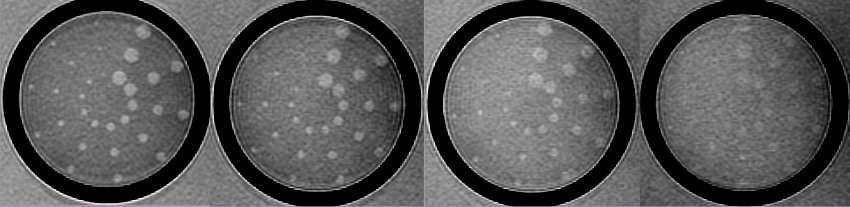

Contrast resolution is usually measured by generating a pattern from a test object that depicts how image contrast changes as the structures being imaged get smaller and closer together. The picture below shows one such set of images produced using the low contrast detectability inserts of the phantom employed in the MRI accreditation program of the American College of Radiology.

Contrast detail curves, which depict the functional relationship between image resolution and contrast resolution, can be produced using this type of data.